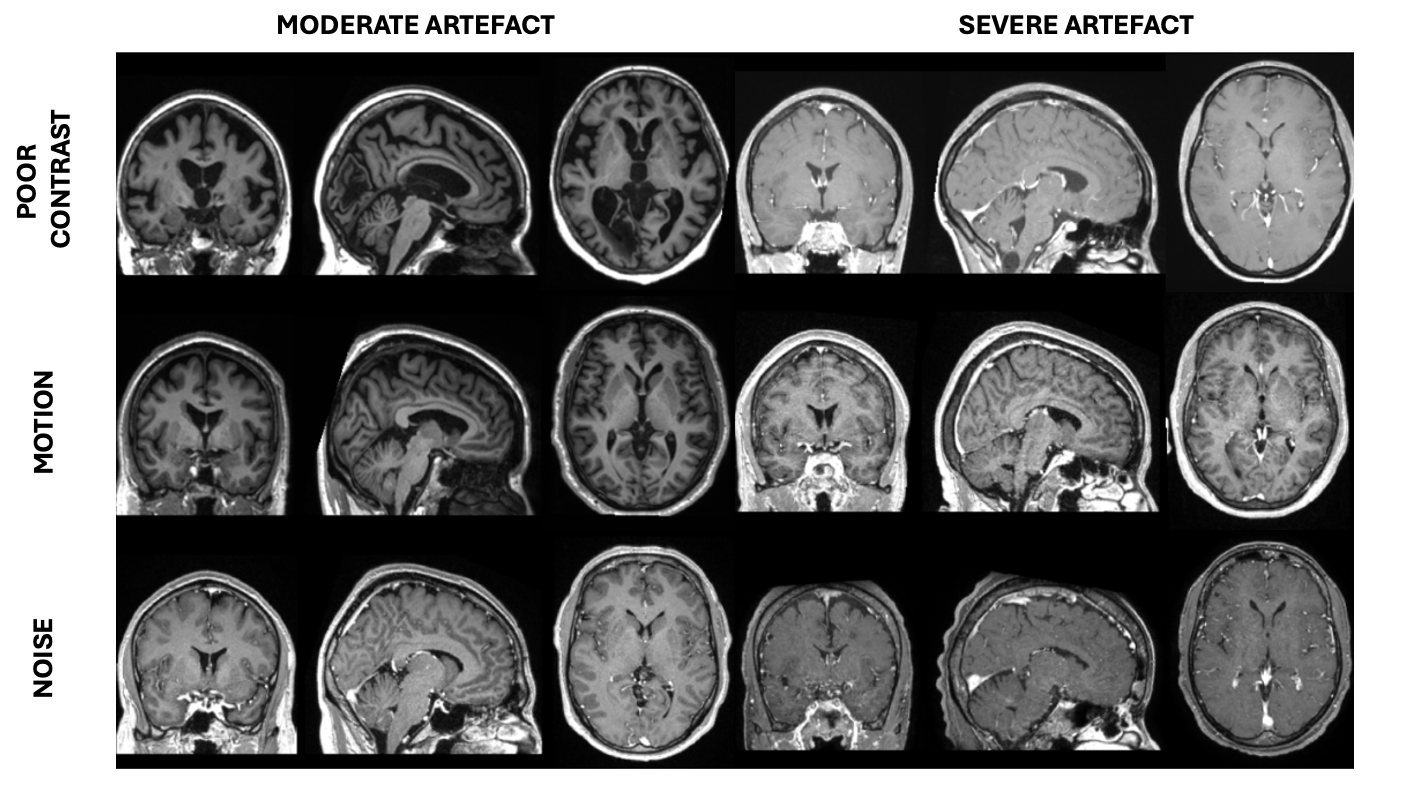

Manual annotations were previously performed by two raters regarding the quality of the 5500 T1w MRIs. Specifically, the contrast, noise and motion characteristics of the images were assessed using a three-level scale (Figure 1). The weighted Cohen’s kappa between the two manual annotators for each of these artefacts is reported in the Appendix (Table A1). Based on the grades attributed to these three characteristics, quality tiers were defined as follows: tier 1 stands for good quality MRI (grade of 0 for the three characteristics); tier 2 for medium quality (one characteristic with a grade of 1 and none with 2); tier 3 for bad quality (one characteristic with a grade of 2). The rules used to define the tiers are summarised in Table 2. A total of 1455 images were categorised as “straight reject” because they were not true 3D T1w MRIs, mainly because they were truncated or segmented images, and were therefore excluded from this study. As a result, we obtained a dataset comprising 4045 images from 3346 patients. The demographic characteristics are shown in Table 1. From these MRIs, we randomly selected 385 images to build our independent test set, which is the same used in (Bottani et al., 2022). Notably, this test set had the same tier distribution as the images within the training and validation set.